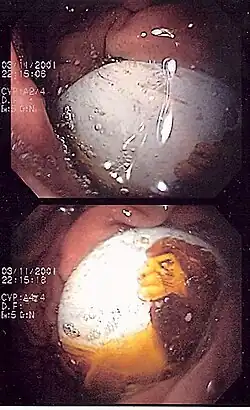

Magnetix

One death and four serious injuries led to the recall of 3.8 million Magnetix building sets in March 2006. The magnets inside the plastic building pieces could fall out and be swallowed or aspirated.[39] In 2009, Luigi Avolio and Giuseppe Martucciello published in The New England Journal of Medicine documenting the effects of magnetic toys ingestion in two children.[40] Since then MEGA Brands has implemented design enhancements to Magnetix, including sonic welding of panels, 100% inspection, gluing magnets into rods, elimination of 3+ labeling in favor of 6+ labeling after it assumed operational control of Rose Art on 1 January 2006. Only safe and improved products are currently on store shelves.[41]